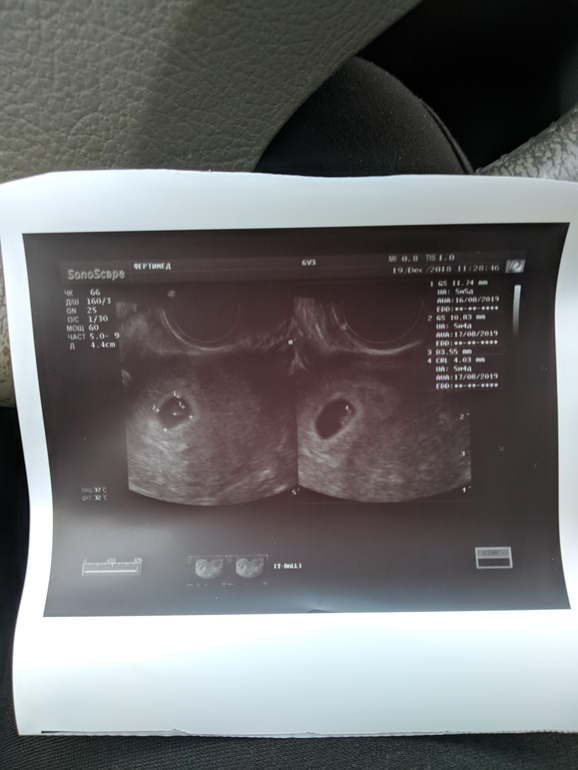

Ну вот и мы дожили до первого УЗИ)

никаких размеров не запомнила, только что все в соответствии со сроком и СБ+. По плану УЗИ должно было быть завтра, но у меня с вечера подозрительно стало колоть с левой стороны, а жт справа, я перепугались и понеслась на УЗИ сегодня, благо милейший Асланбек Русланович всегда найдет 5 минуточек на УЗИ даже если у него все расписано.